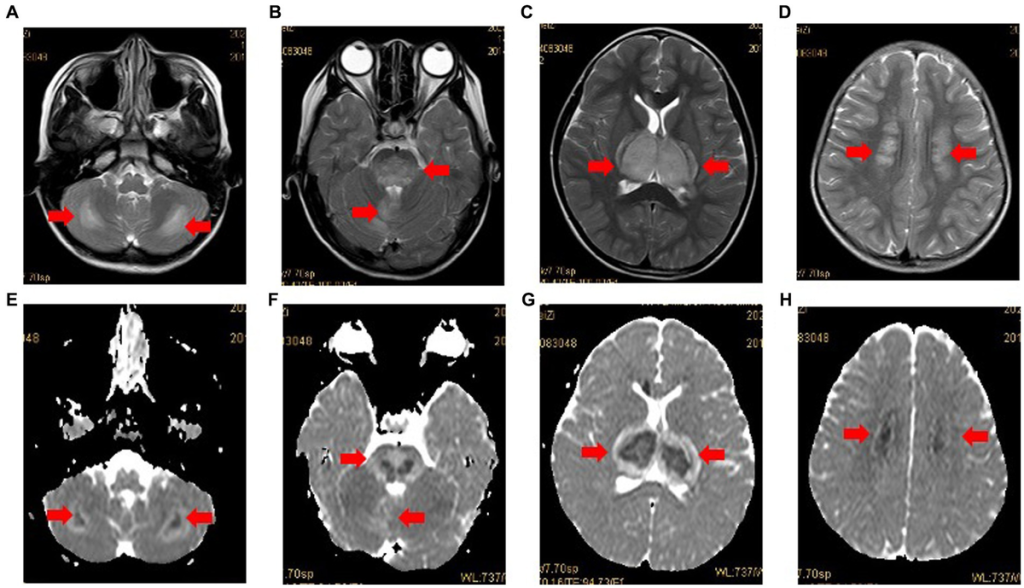

- Magnetic Resonance Imaging (MRI) – The key diagnostic tool. It shows bilateral symmetric lesions in the thalamus, brainstem, and other brain regions.

- The severity of brain lesions seen on MRI